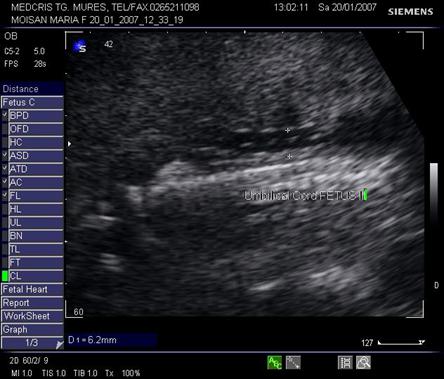

Fig nr 49. Sarcina 19 sapt. ,cu tripleti , biamniotica bichoriala, cu sindrom transfuzor transfuzat la fetii monoamniotici, cu retard de crestere intrauterina si cordon ombilical cu diam . pe jumatate la transfuzor ( intre cele doua calipere ) fata de transfuzat ( fig urmatoare )

Fig nr 50. Cordonul ombilical al fatului transfuzat , dublu fata de cel al transfuzorului, in diametru ( intre calipere )